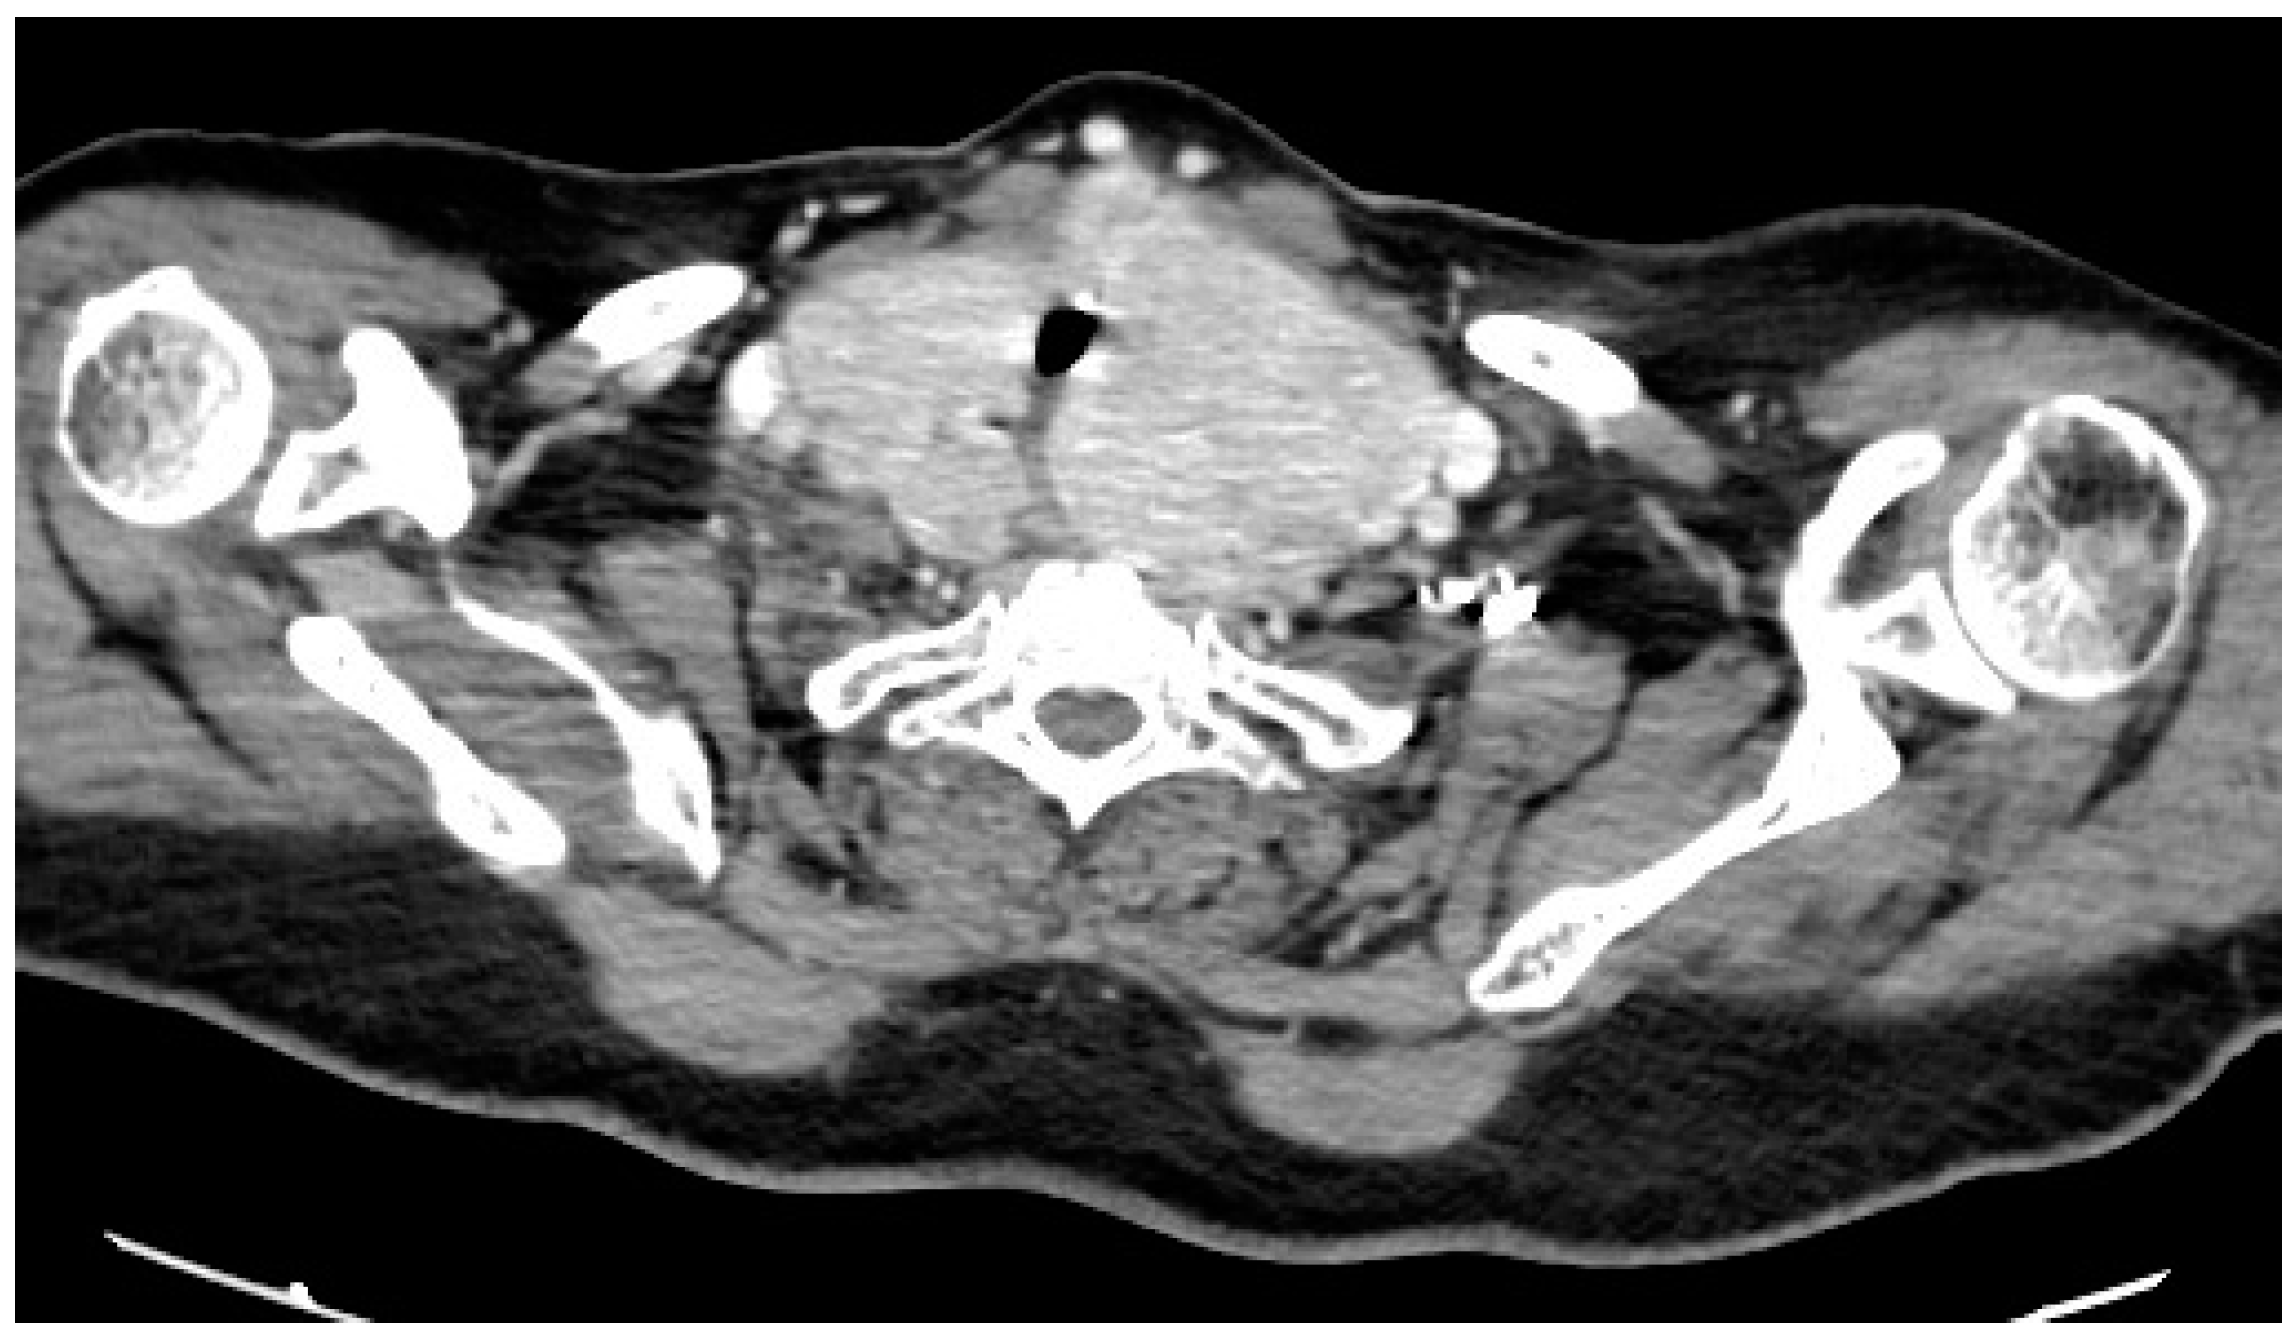

2. Case Description